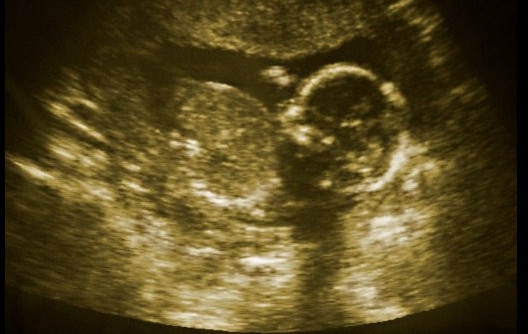

Pasi që ishte vështruar se fetusi 17-javësh zhvillonte një tumor të rrallë në gojë, dukej se fëmija nuk kishte shpresë për të mbijetuar. Mjekët e Spitalit Jackson Memorial kishin zbuluar këtë fluskë të madhësisë së një pjeshke gjatë një ultrazëri të kryer mbi nënën. Ky rast po vërtetohej për hërë të dytë dhe shanset e mbijetesës së foshnjës në lindje ishin pothuajse zero, mendonin specialistët.

Por ata vendosën të mos qëndrojnë pasivë dhe zgjodhën të kryejnë një kirurgji in utero. Duke përdorur një laser të vendosur në mitër nëpërmjet një gjilpëre, shkencëtarët kanë arritur të ndajnë të ashtuquajturin “teratomë të gojës” pa dëmtuar fytyrën dhe shëndetin e ardhshëm të foshnjës.

Një intervenim i tillë i suksesshëm përbën një zbulim të madh mjekësor. Me moshë 20-muajshe, foshnja Leyna Mykaella Gonzalez mban vetëm një shenjë të vockël në buzën e saj.